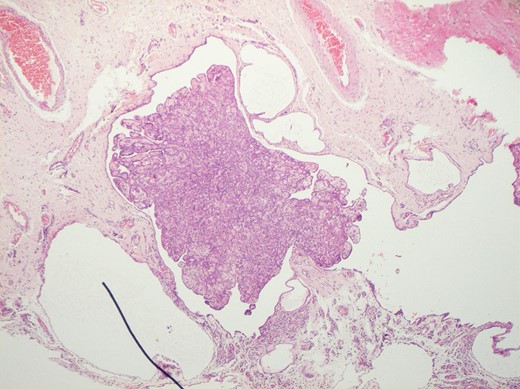

Histological features of the specimen were that of a fibrous cyst wall covered by cuboidal cells with bland nuclei (Fig. 1). Within the cystic space, there were branching, papillary structures with a fibrovascular core, lined with a single layer of bland cuboidal cells (Fig. 2). The stroma was oedematous and hyalinised. No sub-epithelial invasion was seen. There was no unequivocal cytologic atypia or atypical mitosis.

H&E staining of the specimen demonstrating branching, papillary structures with a fibrovascular core lined with a single layer of bland cuboidal cells.